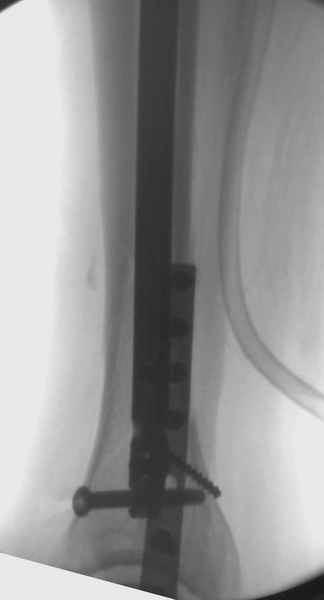

Здесь мы использовали новый Synthes Nail с дополнительными дырками, в проксимальной части 4: по две косых и поперечные (один стандартный а другой динамический), в дистальной части две поперечные, прямая и косая. Вес больного более 120 кг, нагрузку начнем через месяц.

Djoldas Kuldjanov, MD

St. Louis University Medical Center